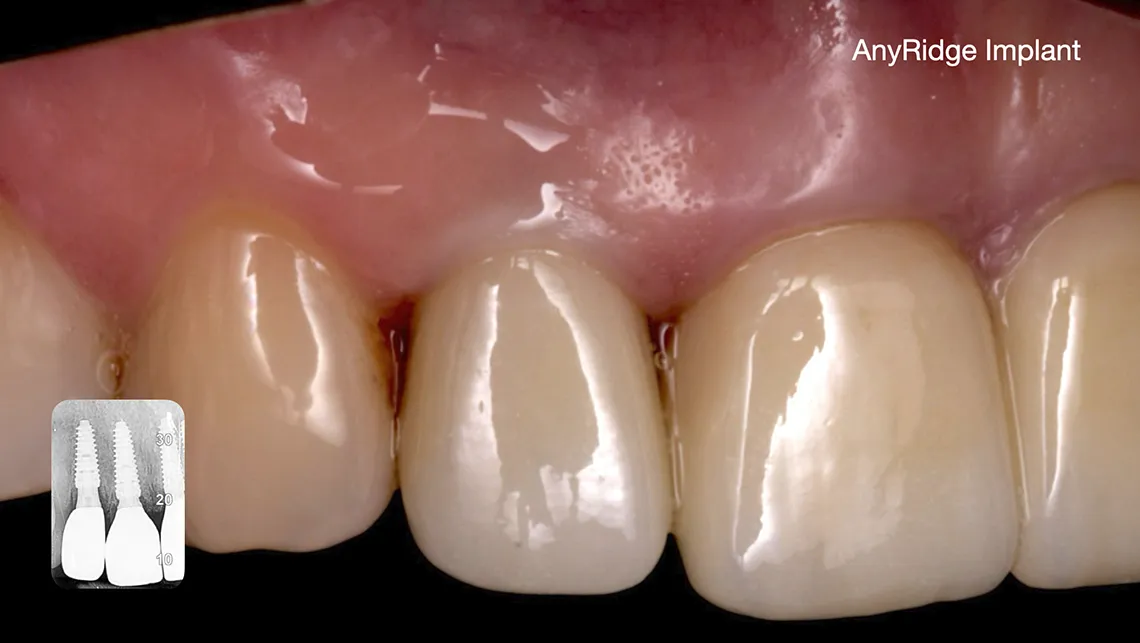

En el contexto actual de la implantología, donde se priorizan procedimientos mínimamente invasivos y los resultados predecibles, la oseodensificación se consolida como una herramienta clave para todos aquellos clínicos avanzados, con una base científica sólida y un potencial de aplicación en continuo crecimiento (figura 11, 12, 13, 14, 15, 16 y 17).

Fig. 15. SPOT, implante instalado

Fig. 16. Implante cicatrizado a 9 semanas

Fig. 17. SPOT. Restauración final